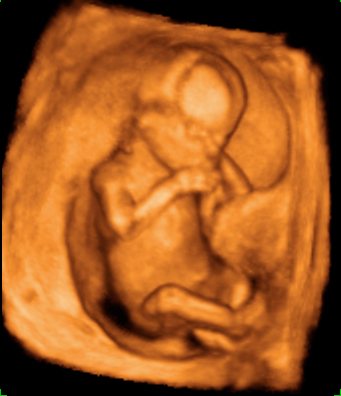

Aspecto de un bebé de 12 semanas tomado en ecografía 3D.

Se pueden apreciar con toda claridad la cabeza (aún más grande en proporción, que el resto del cuerpo), el tronco, las extremidades y el cordón umbilical. El niño ya se apoya con la espalda en el útero materno, lo que facilita la exploración por parte del ecografista.

Ecografía Embarazo 4D - SEMANA 12